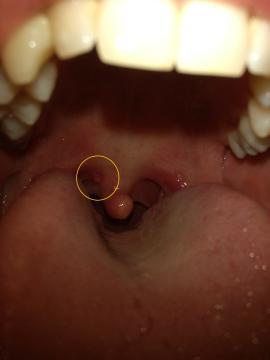

Pro větší náhled klikněte na obrázek

Dobrý den,před nedávnem se mi objevil malý hrbolek v krku a doprovázeli ho mírné bolesti v krku. V tuto dobu bolesti krku už nejsou, ale hrbolek se změnil ve váček (viz foto). Bohužel nemám čas zajít k doktorovi a myslím si že to bude triviální věc. Jen mi váček vadí v krku a nevím jak se ho zbavit. Poradíte mi ? Děkuji Vám za odpověď.

Dobrý den, na fotce jsou patrná i začervenání patrových oblouků, nejspíše vlivem virového zánětu, cystičky u uvuly jsou reakcí na tento zánět, samy postupně zmizí, doporučuji kloktadla (odvar z heřmánku), cucavé bonbóny s antiseptickým účinkem (např. Strepsils).